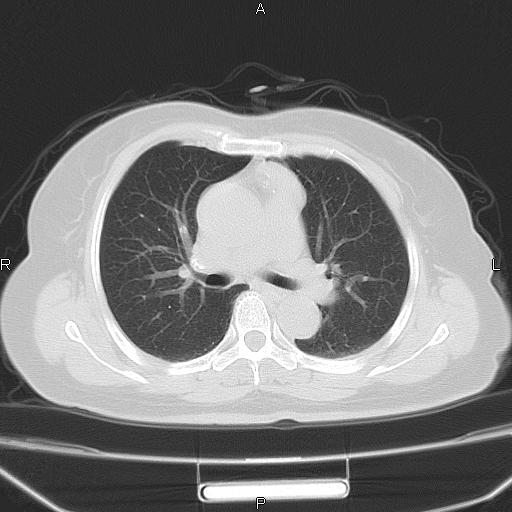

女、63Y 双眼睑下垂,早轻晚重。 胸腺瘤???

结果胸腺瘤